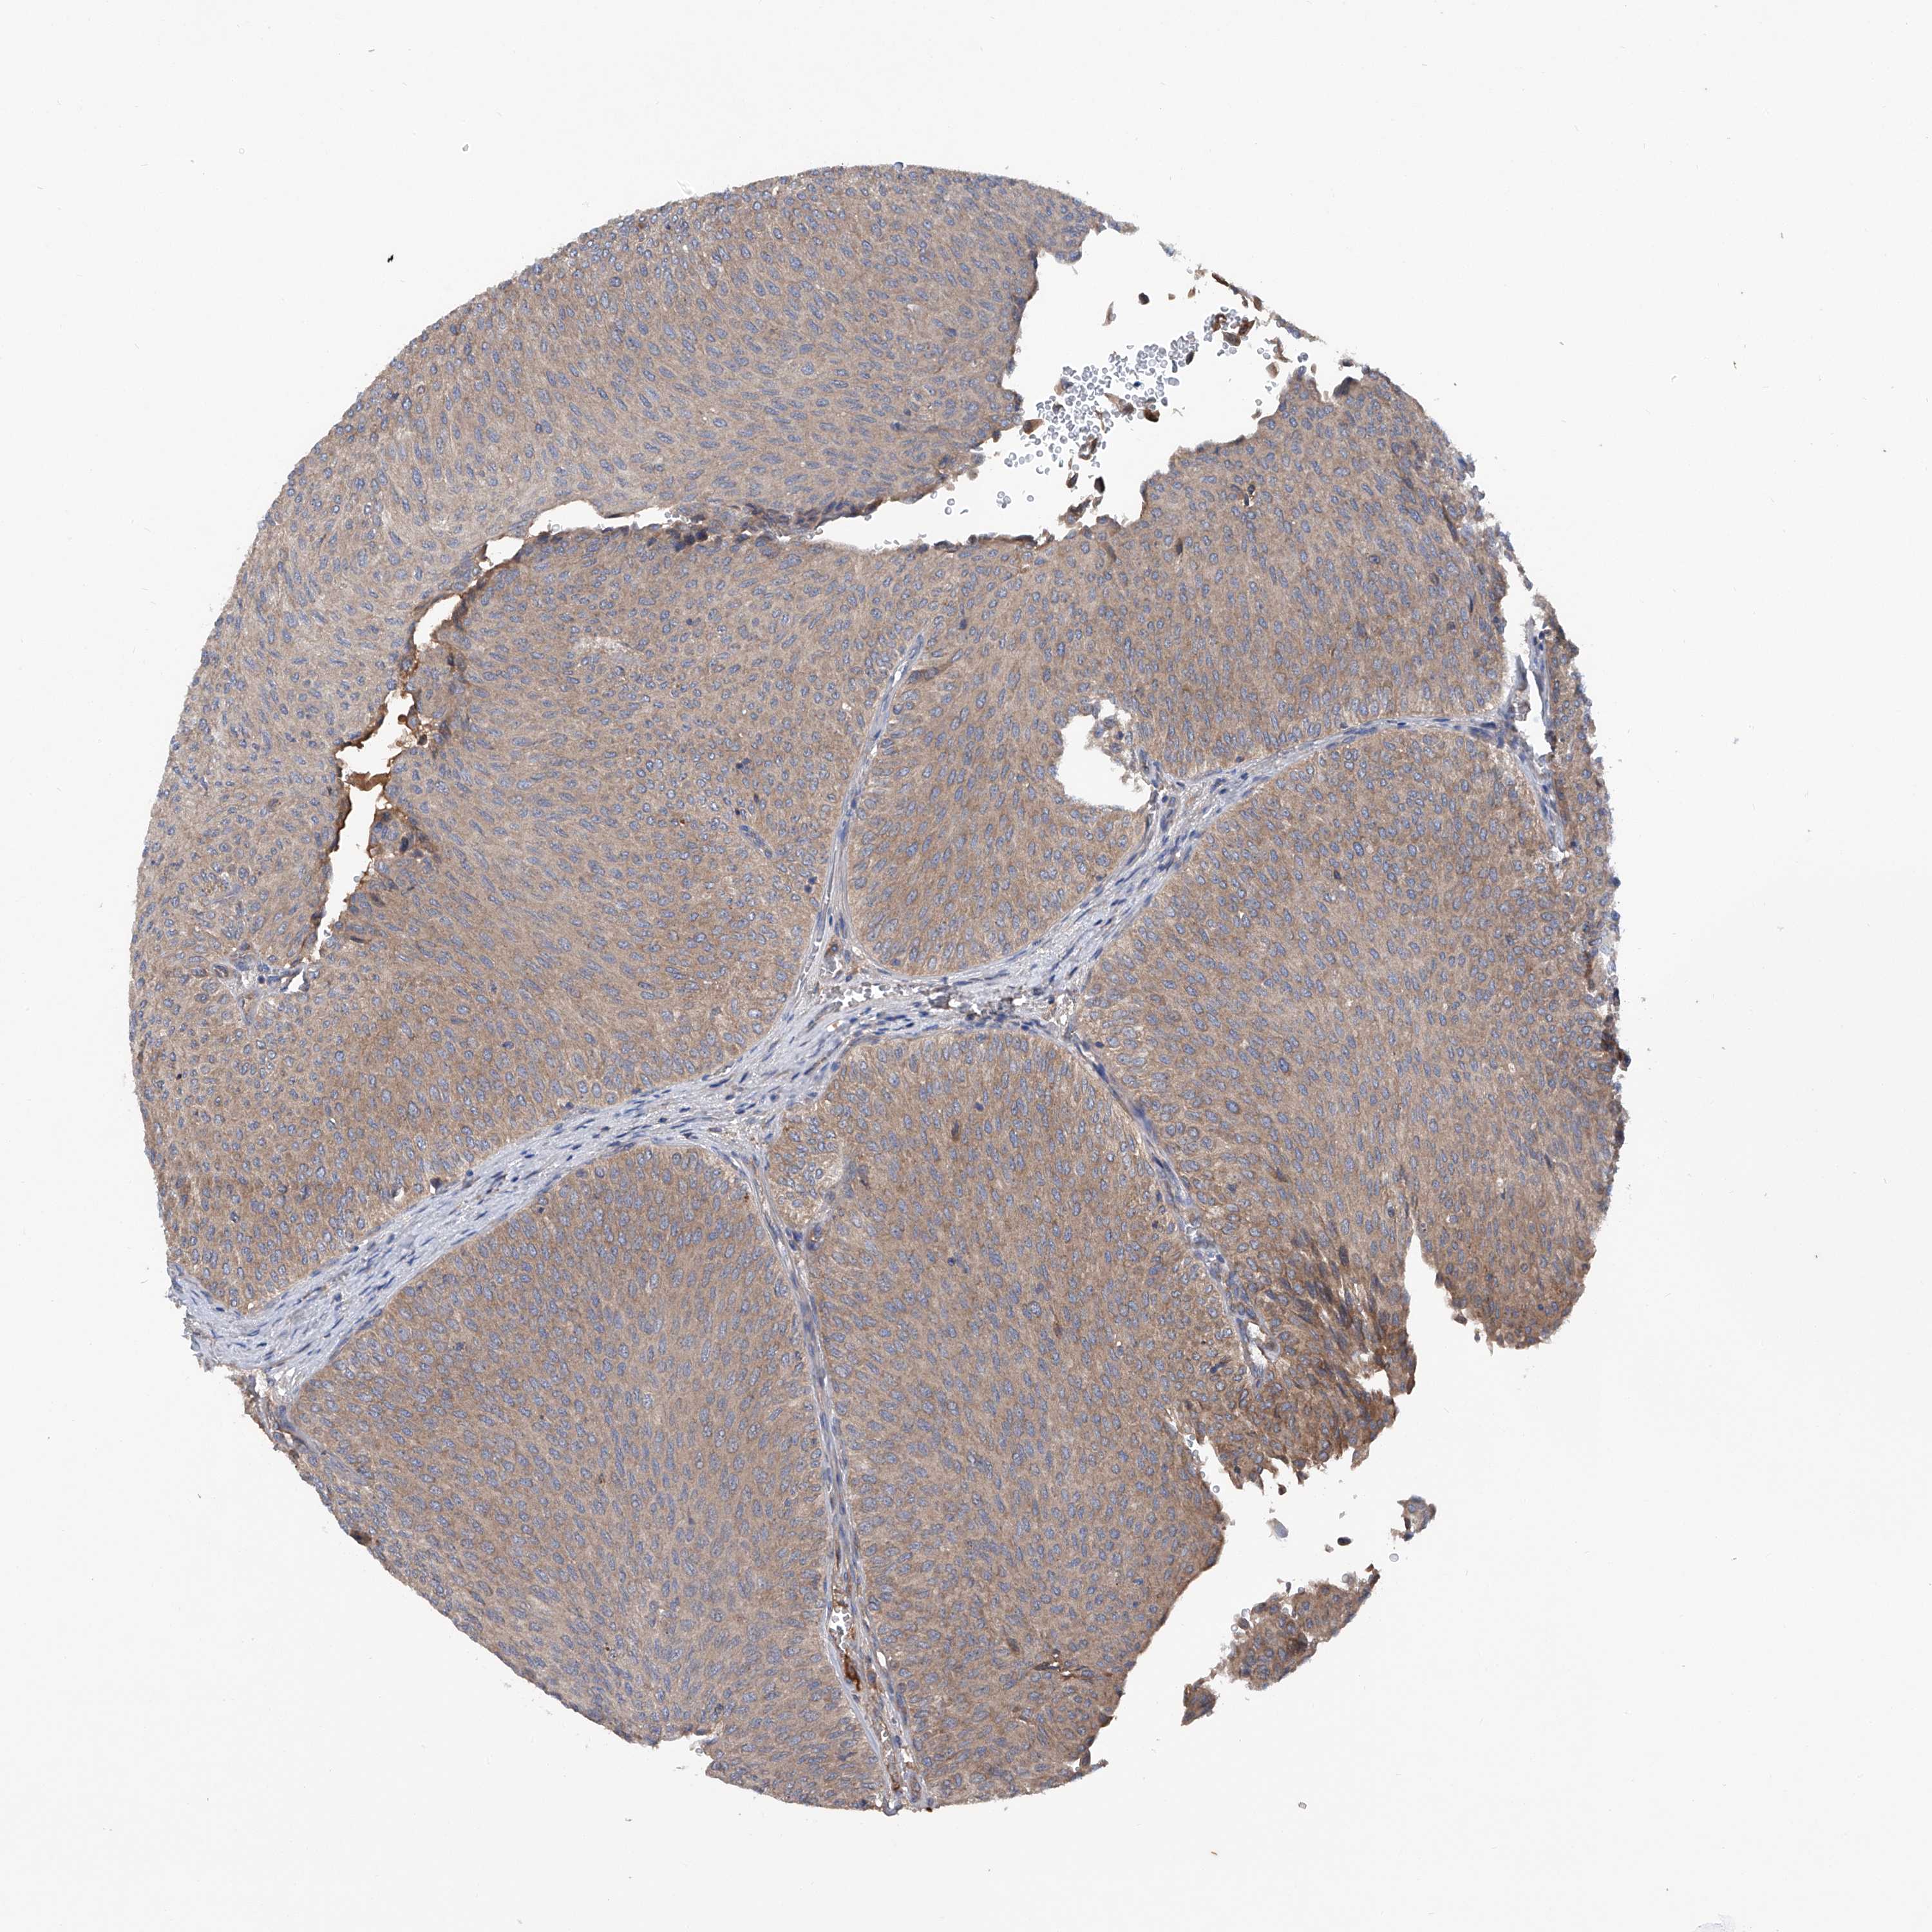

UROTHELIAL CANCER - Protein expressioni

A mouse-over function shows sample information and annotation data. Click on an image to view it in a full screen mode. Samples can be filtered based on level of antibody staining by selecting one or several of the following categories: high, medium, low and not detected. The assay and annotation is described here.

Note that samples used for immunohistochemistry by the Human Protein Atlas do not correspond to samples in the TCGA dataset.

Antibody stainingi

Antibody staining in the annotated cell types in the current human tissue is reported as not detected, low, medium, or high, based on conventional immunohistochemistry profiling in selected tissues. This score is based on the combination of the staining intensity and fraction of stained cells.

Each image is clickable and will lead to virtual microscopy that enables deeper exploration of all samples and also displays staining intensity scores, fraction scores and subcellular localization as well as patient and tissue information for each sample.

Antibody HPA031608

Antibody HPA031609

Antibody HPA031610

Urothelial carcinoma, Low grade

Urothelial carcinoma, High grade